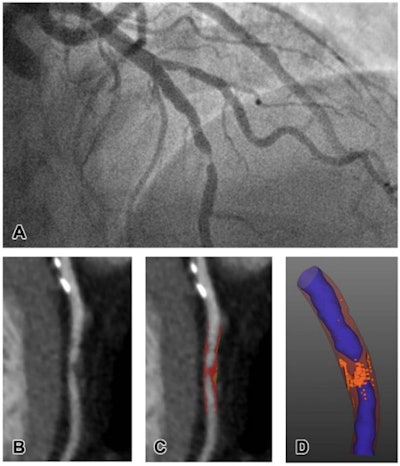

Representative images of CT plaque analysis demonstrate differences between type 1 and type 2 myocardial infarction. (Left panel) Images in a 42-year-old man diagnosed with type 1 myocardial infarction. (A) Image from invasive angiography demonstrates severe stenosis in the distal left anterior descending artery. (B) CT coronary angiogram, curved planar reformation, (C) quantitative plaque analysis, and (D) three-dimensional quantitative plaque analysis demonstrate a high burden of low-attenuation plaque. Right panel: Images in a 74-year-old man diagnosed with type 2 myocardial infarction. Images courtesy of the RSNA.Meah and colleagues sought to confirm whether particular kinds of heart plaque characterized on CTCA could help clinicians determine the type of heart attack a patient was suffering via a study that included 327 patients. Of the total cohort, 155 had type 1 infarction, 36 had type 2, and 136 had chest pain but no heart attack.